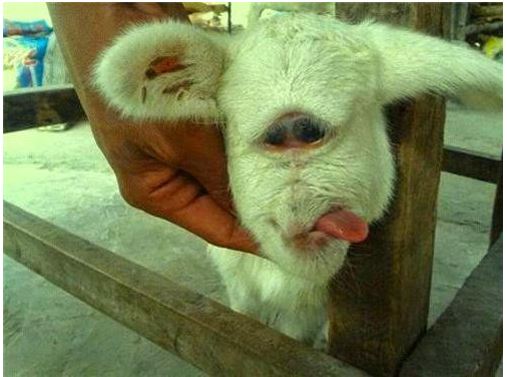

Điều đặc biệt là dị tật này không giới hạn ở con người, mà các loài động vật cũng có khả năng gặp phải. Các chuyên gia cho biết, tỉ lệ mắc cyclopia ở động vật là khoảng 1/16.000 ca sinh nở. Theo thống kê, người ta đã bắt gặp những con mèo, cừu, lợn, hay thậm chí cả... cá mập - tất cả được sinh ra với độc một con mắt.

Dị tật này không giới hạn ở con người, mà các loài động vật cũng có khả năng gặp phải.